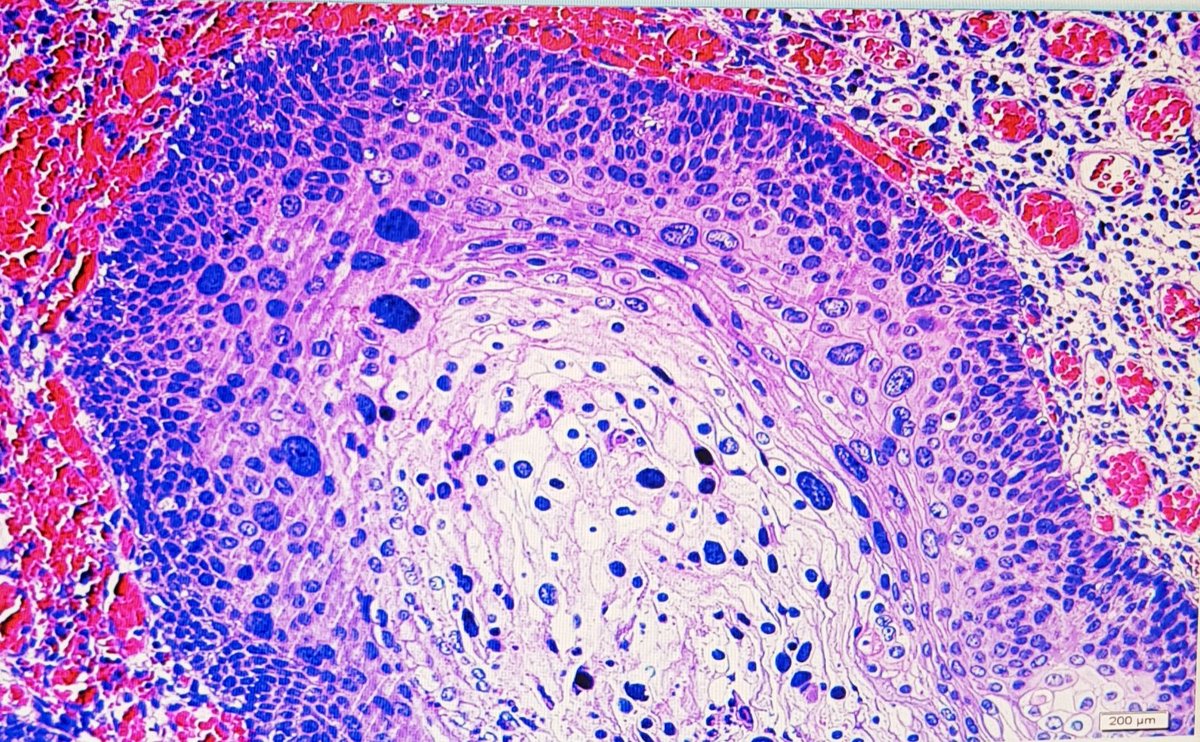

Incredibly thankful and excited to announce that I’ll be joining the faculty @MGHPathology @harvardmed this Spring! Thank you to all my mentors and colleagues here and @PennPathLabMed where I trained as a resident - I learn more from you each day! #gynpath #BreastPath #gupath